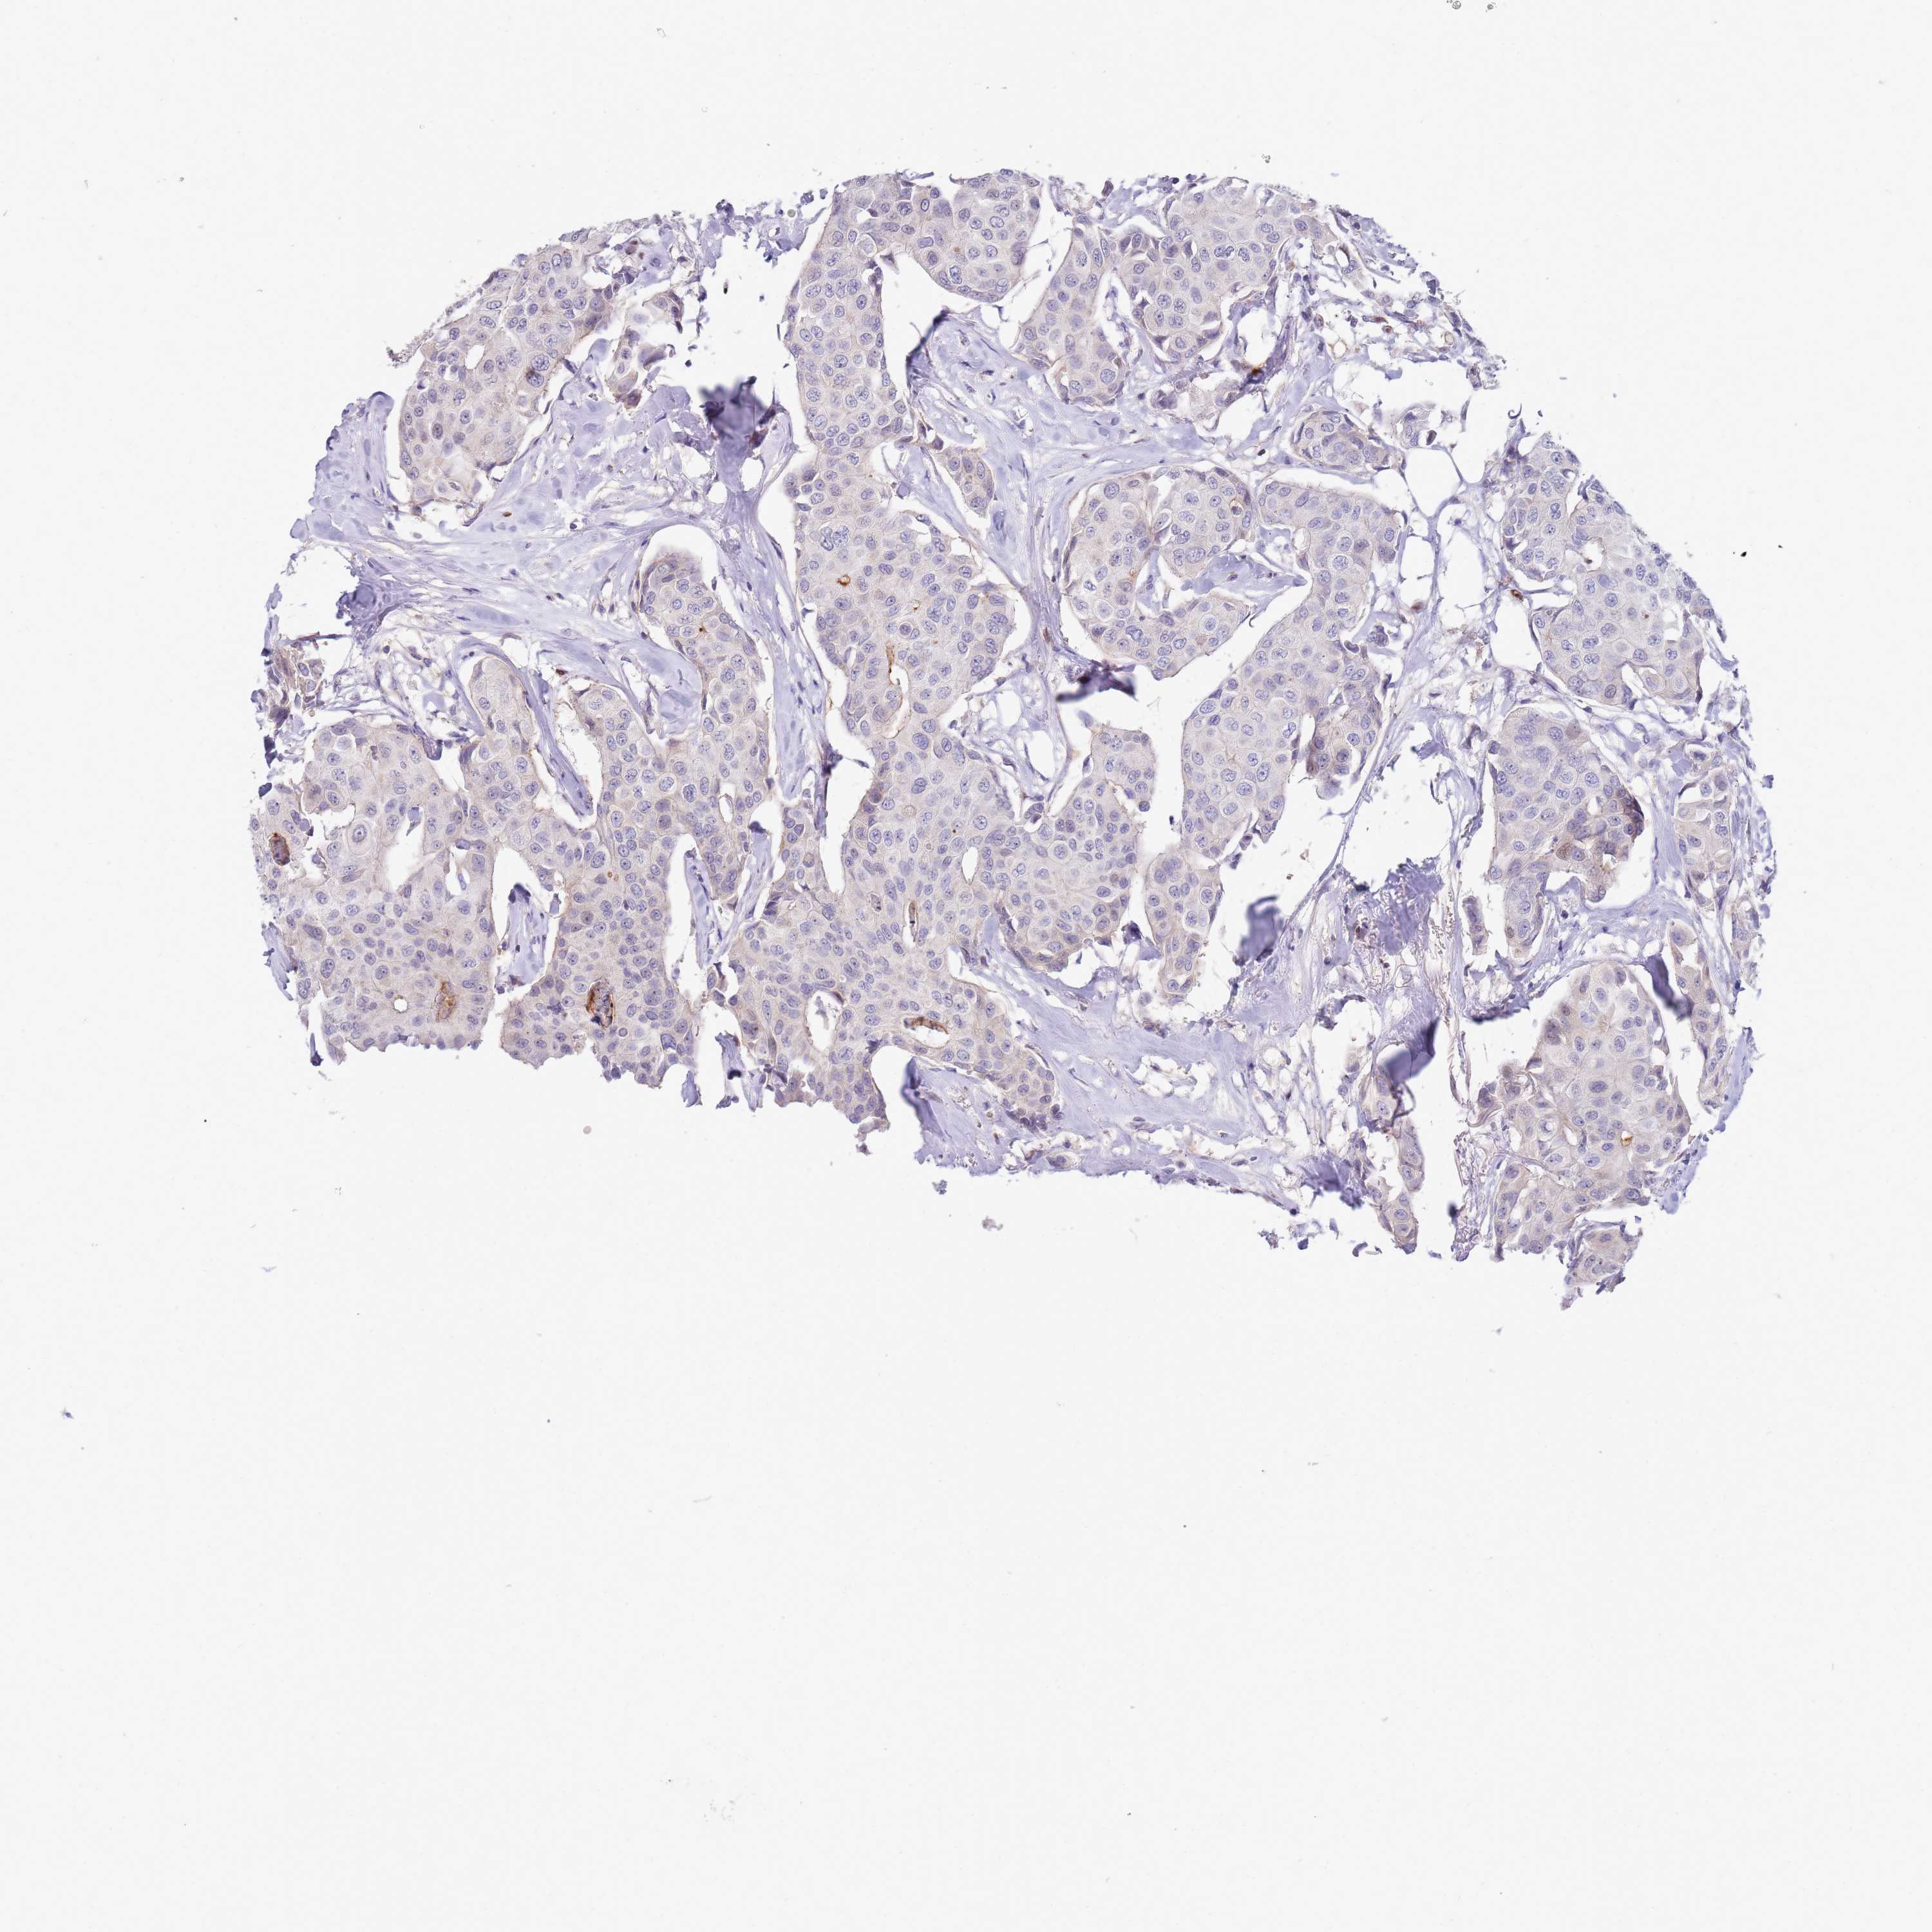

CANCER BREAST CANCER Show tissue menu

Breast cancer

Human cancer